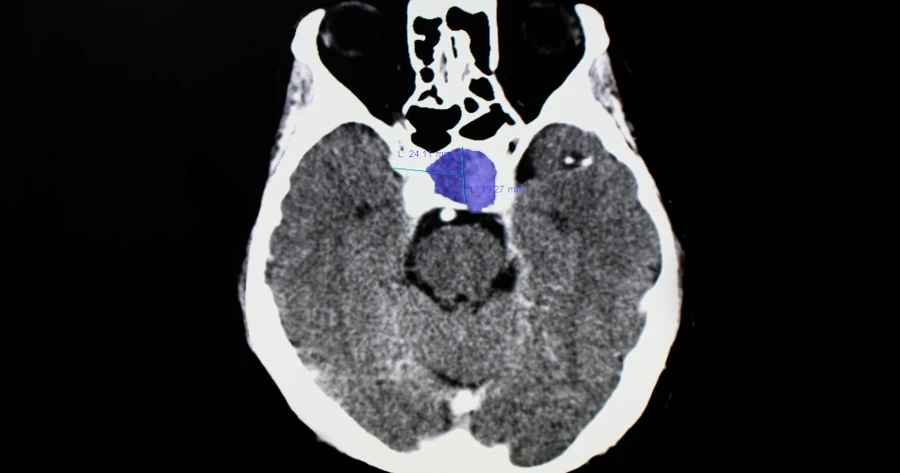

Këto ndryshime të papritura në trup shpesh keqinterpretohen, por mund të jenë sinjali i parë i një tumori beninj që ndikon fuqishëm në hormonet e organizmit

Simptoma të pazakonshme që lidhen me balancën hormonale dhe shfaqen papritur, si mungesa e menstruacioneve, rrjedhja e qumështit nga gjoksi te gratë që nuk janë lehona, disfunksioni erektil te meshkujt apo madje edhe rritja e pazakontë e gjinjve (ginekomastia) – mund të jenë shenja të hershme të një tumori të hipofizës.